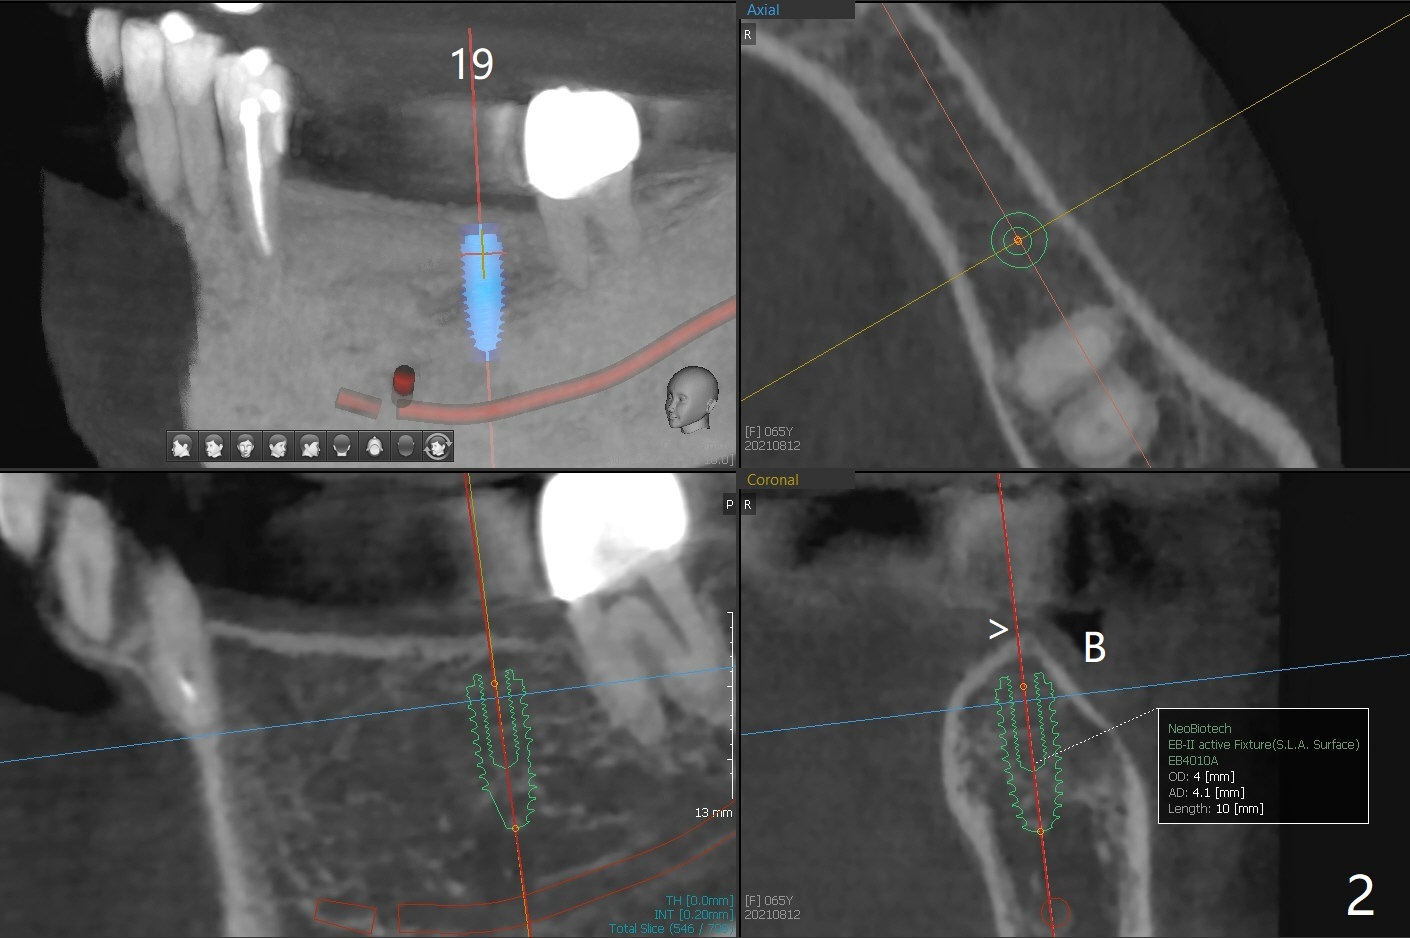

A 65-year-old woman returns for 19-21 implant FPD 9 months post cementation at #30 (Fig.1). The bone density is 600 units at #19 (Fig.2). To place a 4x10 mm implant, underdrilling is required (the last drill will be 3 mm). The implant at #21 will be expected to be 3.5x11.5 mm (Fig.3). Since the ridge at #19 and 21 is narrow (Fig.2,3 arrowheads), the keratinized gingiva should be narrow. Incision will be made to save the latter. Take photos of the erythematous ridge, as related to denture fungal infection.